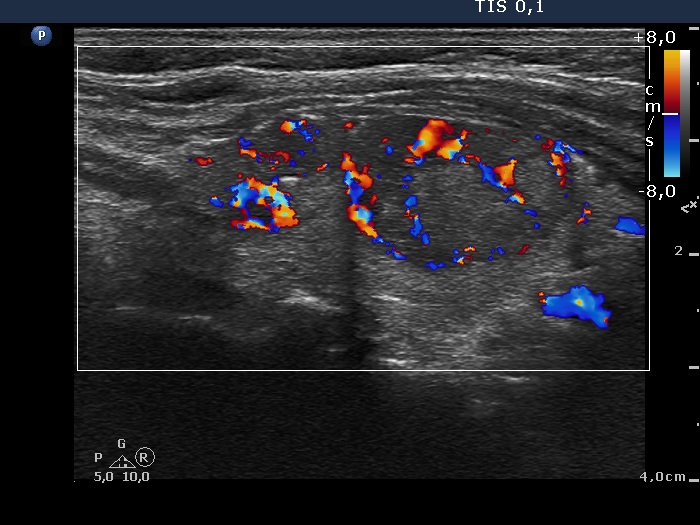

Right lobe, longitudinal scan

Right lobe, longitudinal scan, color Doppler mode. The upper nodule (left in the image) shows intranodular vascularization while the larger, lower nodule (right in the image) presents both perinodular and intranodular vascularization.